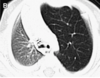

What congenital lung malformation is shown in this CT scan of a 2-month old girl?

Congenital pumonary aiway malformation (CPAM)

The arrow is pointing to a large systic mass